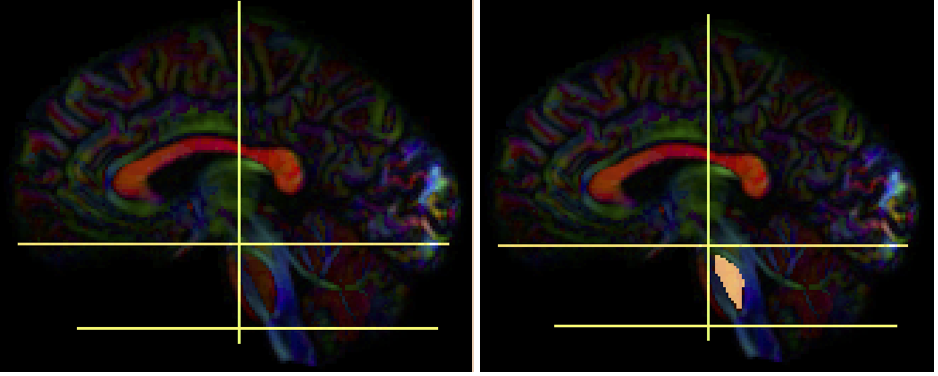

- Create two separate sagittal seed regions (at approx. sagittal slice 76 and 80), one for each side

- Create two separate sagittal ROI regions (lateral to the seed regions) (at approx. coronal slice 73 and 83), one for each side.

- In the region list, check only the left seed region, then run fiber tracking. Based on this output, ROA placement will be clearer.

- Create one ROA region and draw three different regions:

- on a coronal slice anterior to the seed region

- on an axial slice superior to the seed region

- on an axial slice inferior to the seed region

- Check all seed regions and ROA region. Perform fiber tracking.

- Under the tract list, make sure only the desired tract is checked and highlighted in purple. Save region, tract, and density files.

Confusing – does this cross midline? Is there L/R? I would suggest just two ROIs rather than two seeds, two ROIs, 3 exclusion regions.

Need anatomical descriptions – where is seed placed? Where are ROAs placed? I assume we want to reference exclusion regions in reference to cerebellum anatomy.